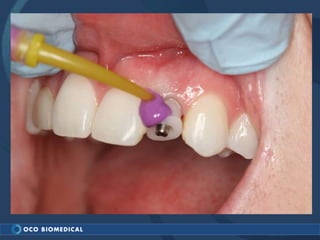

A 3.0mm dental implant was placed to replace congenitally missing maxillary lateral incisors. Dr. Tim Kosinski used a 1.8mm pilot bur and tissue punch to prepare the osteotomy site, then placed the implant by hand and seated it with a torque wrench. After ensuring the implant trajectory was within the restorative envelope, an acrylic coping was placed for temporary fabrication. At the 1 week post-op appointment, excellent soft tissue response and papilla formation were observed, and a final impression was taken to send to the lab for crown fabrication.